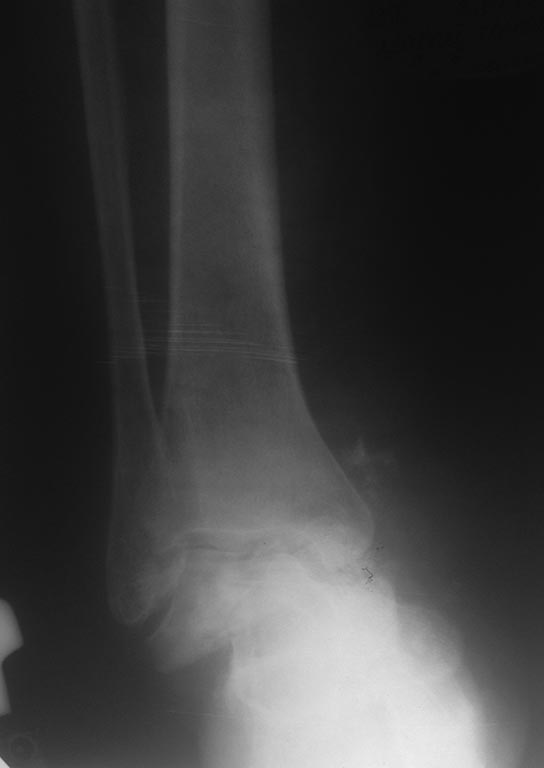

Перелом таранной кости. 56 лет женщина, подвернула правую стопу 06.07.15 не придала этому значения, продолжала ходить.

Постепенно стали усиливаться боли и деформация. 08.07.15 обратилась в поликлинику, больной сделан рентген . Из анамнеза страдает сахарный диабетом с 2002 года, онкопатологию отрицает. Хотелось бы узнать, уважаемые коллеги, о тактике лечения данной пациентки.

Такой переломо-вывих мог не беспокоить разве что при выраженной диабетической полинейропатии. Прогноз скверный. Вероятен исход в стопу Шарко.